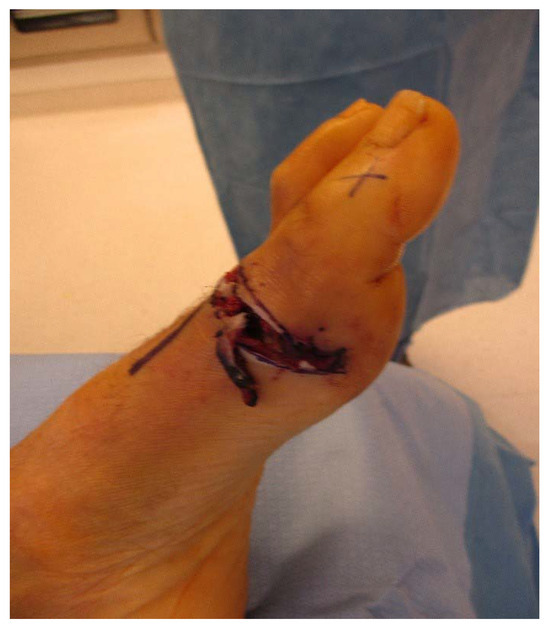

A Novel Technique for Soft-Tissue Defect Repair After Traumatic Rupture of the Extensor Hallucis Longus Tendon

by Ellianne Nasser, William Clark and Michael Gibboney

J. Am. Podiatr. Med. Assoc. 2021, 111(3), 18066; https://doi.org/10.7547/18-066 - 1 May 2021

Background: Surgical repair of extensor hallucis longus (EHL) tendon rupture with a concomitant capsular defect has not been reported in the literature. This case presents a novel approach to EHL tendon rupture repair along with repair of a first metatarsophalangeal joint capsule defect. [...] Read more.

Background: Surgical repair of extensor hallucis longus (EHL) tendon rupture with a concomitant capsular defect has not been reported in the literature. This case presents a novel approach to EHL tendon rupture repair along with repair of a first metatarsophalangeal joint capsule defect. Methods: A case study is presented of a 61-year-old man with a traumatic EHL tendon rupture and capsular defect treated with an EHL tendon turndown flap and tenodesis to the extensor hallucis brevis and capsularis tendons with autograft flap reconstruction of the first metatarsophalangeal joint capsule. Discussion: A 61-year-old man presented with an acute traumatic EHL tendon rupture and first metatarsophalangeal joint capsule compromise after a chainsaw injury. He subsequently lost dorsiflexion of his hallux, and magnetic resonance imaging confirmed a 2.2-cm gap in the EHL tendon. He was treated with an EHL tendon turndown flap and tenodesis to the extensor hallucis brevis and capsularis tendons to reestablish dorsiflexion to the hallux. The injury was noted to infiltrate the first metatarsophalangeal joint capsule and was treated with an autograft of the first metatarsophalangeal joint capsule for a capsular defect. At 1-year follow-up the patient has regained dorsiflexion of the hallux and is back to activities such as snow skiing without pain. Conclusions: Ruptures of the EHL tendon with first metatarsophalangeal joint capsule defects have not been reported in the literature. Herein, a novel approach was used to reestablish physiologic function to the EHL tendon and provide sufficient coverage of the first metatarsophalangeal joint. (J Am Podiatr Med Assoc 111(3): 1-5, 2021) Full article